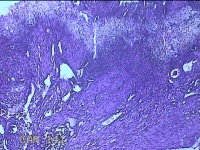

宫腔粘连带

标本名称

大体所见

灰白暗红色不规则碎组织1.3x1.2x0.3cm一堆。

图4